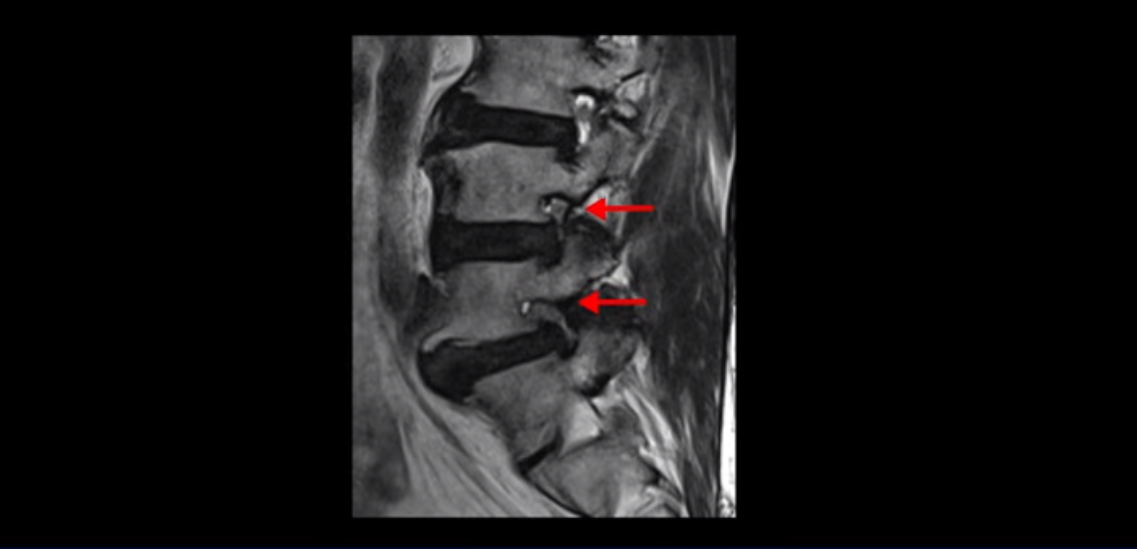

이분은 허리 다섯 마디 중 4번 5번, 5번 1번에 감압술로 눌린 신경을 풀어주는 수술을 받았습니다.

후관절을 떼어낸 흔적이 보입니다.

5번 1번도 왼쪽 후궁을 열고 수술 받았습니다.

하지만 중심성 협착은 여전히 심한 상태입니다.

이분은 오른쪽, 왼쪽 다리에 모두 방사통이 심하고 왼쪽 다리에 마비 증상, 즉 풋드랍(족하수) 증상이 있습니다. 왼쪽 신경 가지가 빠져나가는 추간공을 보면 두 마디가 좁아져 있습니다.

이런 신경 구멍이 좁아져 있는 걸 협착이라고 합니다.

이미 앞선 두 번의 수술로 뼈와 인대 등을 일부 제거해서 안정성이 떨어진 상태에서 추가로 수술하려니까 척추가 너무 불안정해져 무너질 게 걱정되니까 이번에는 나사 박는 유합술을 권유 받은 겁니다. 이런 환자분들의 방사통과 마비 증상이 어떻게 수술 없이 좋아질 수 있을까요? 치료는 어떻게 하는 걸까요?